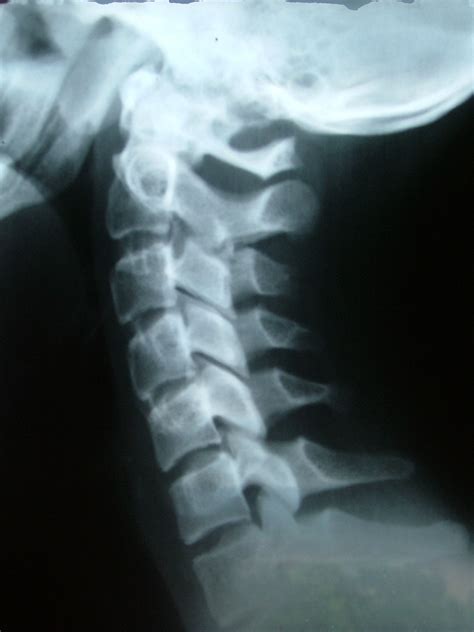

Osteoarthritis - Texas Pain Physicians